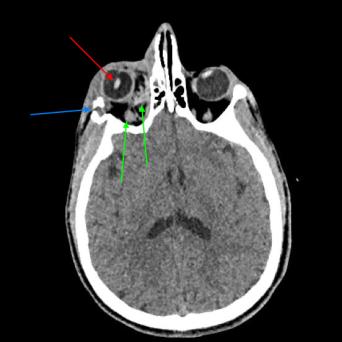

Extension et rehaussement de cils : complications dermatologiques et oculaires

Fortement relayées sur les réseaux, les nouvelles pratiques esthétiques sur les cils sont en plein essor. Sérums, pose d’extensions ou encore dispositifs aimantés peuvent être à l’origine de symptômes et complications périoculaires et oculaires. Pour les médecins généralistes, il est essentiel de reconnaître les effets indésirables irritatifs ou allergiques de ces techniques afin d’orienter les patients.